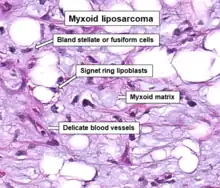

| Histopathologic image of myxoid liposarcoma arising in the thigh. H & E stain. | |

.JPG.webp) Micrograph of myxoid liposarcoma. H&E stain